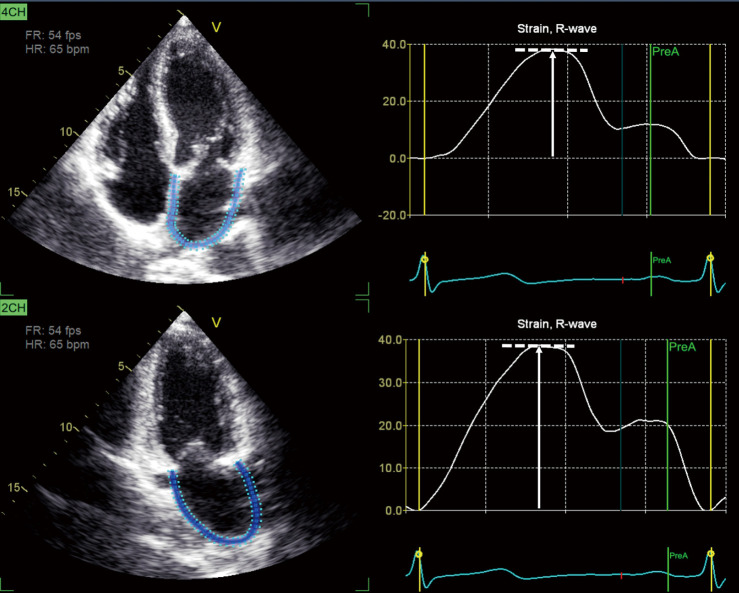

本研究探讨了左心房(LA)储液池应变在左侧心力衰竭(HF)情况下作为右室(RV)功能障碍(RVD)的独立决定因素的潜力。我们在2021年至2023年间从中国医科大学第一医院招募了301例HF患者(年龄61.1±10.7岁,男性71.1%),包括减少(47.8%)和保留射血分数(EF)(52.2%)表型的代表性样本。每位参与者都接受了全面的经胸超声心动图检查。常规超声心动图测量左室(LV) EF和肺动脉收缩压(PASP),二维散斑跟踪超声心动图量化左室整体纵向应变(LVGLS)、左室储层应变和左室游离壁应变。该队列显示RVD患病率为48.5%(定义为RV游离壁应变< |20%|)。RVD与较高的体表面积[比值比(OR) 12.01]和PASP (OR 1.02),较低的LVEF (OR 0.92), LVGLS (OR 1.35)和LA库菌株(OR 0.82)相关(均P值)

This study examined the potential of left atrial (LA) reservoir strain to be an independent determinant of right ventricular (RV) dysfunction (RVD) in the context of left-sided heart failure (HF). We recruited 301 patients with HF (age 61.1±10.7 years; 71.1% male) from The First Hospital of China Medical University between 2021 and 2023, comprising a representative sample of both reduced (47.8%) and preserved ejection fraction (EF) (52.2%) phenotypes. Each participant underwent comprehensive transthoracic echocardiography. Conventional echocardiography measured left ventricular (LV) EF and pulmonary artery systolic pressure (PASP), and two-dimensional speckle tracking echocardiography was applied to quantify LV global longitudinal strain (LVGLS), LA reservoir strain, and RV free wall strain. The cohort demonstrated a 48.5% prevalence of RVD (defined as RV free wall strain < |20%|). RVD was associated with higher body surface area [odds ratio (OR) 12.01] and PASP (OR 1.02), lower LVEF (OR 0.92), LVGLS (OR 1.35), and LA reservoir strain (OR 0.82) (all P values <0.05). Critically, LA reservoir strain (OR 0.83; P<0.001) remained independently associated with RVD even after adjustments were made for age, sex, body surface area, atrial fibrillation, diabetes, hypertension, coronary artery disease, LVEF, LVGLS, and PASP. Thus, in left-sided HF, LA reservoir strain independently predicts RVD irrespective of LVEF or PASP, highlighting the critical role of LA function in RVD.